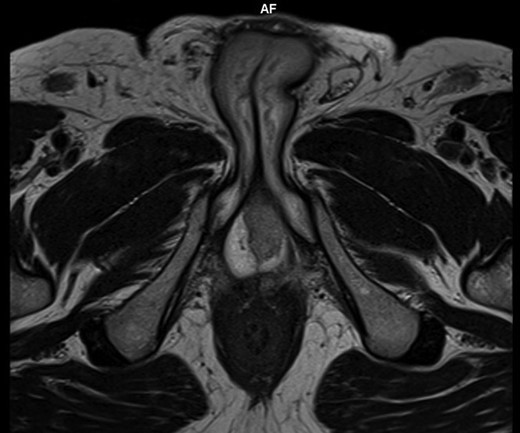

A 60-year-old circumcised male with poorly controlled diabetes mellitus Type 2 presented to the outpatient clinic for 10 days history of redness and painful swelling of the distal penile shaft near the base and fever of 39°C associated with dysuria and frequency. The patient denied any recent sexually transmitted disease, trauma, urethral instrumentation or cavernosal injection. His past medical history was unremarkable except for poorly controlled diabetes (last HBA1C of 11.5% (normal: 4–5.6%). Physical examination revealed edema, induration and tenderness in the left proximal penile shaft with no skin breaks. The testicular and epididymal, digital rectal examinations were normal. No dyspnea or a cough or other complaints. Laboratory examination revealed WBCof 14 000/mm3 with left shift,CRP of 102 mg/L, random blood sugar 380 mg/dL, Urine analysis showed 2–3 WBC per high power field, other blood investigations were all within their normal range. He underwent an MRI of the penis that showed a septated and enhancing structure of 2.2 cm in the posterior aspect of the left corpus cavernosum, worrisome for an intracavernosal abscess that impinges on the adjacent urethra (Fig. 1).

Axial T2 W images of penis showed a well-defined septated area of 2 cm in the posterior aspect of left corpus cavernosum.